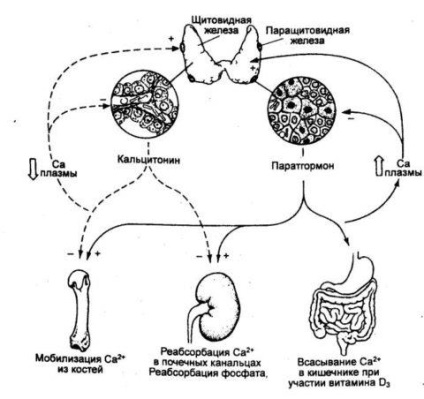

Glandulae parathyroideae titkos biológiailag aktív anyagok, amelyek szabályozzák a kalcium és a foszfor anyagcserét. A diszfunkció lehet a készítmény, a túlzott és az elégtelen mennyiségű PTH.